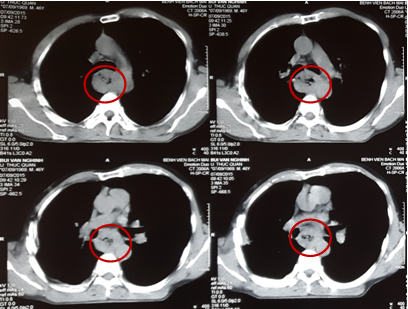

Chụp lại phim cắt lớp vi tính ngực: Hình ảnh khối u thực quản đoạn 1/3 giữa giảm kích thước so với trước điều trị. Thành thực quản dày không đều đoạn 1/3 giữa, chỗ dày nhất 8 mm.

Hình 5: Hình ảnh dày thành thực quản đoạn 1/3 giữa sau xạ trị và 2 chu kì hóa chất ( vòng tròn đỏ).